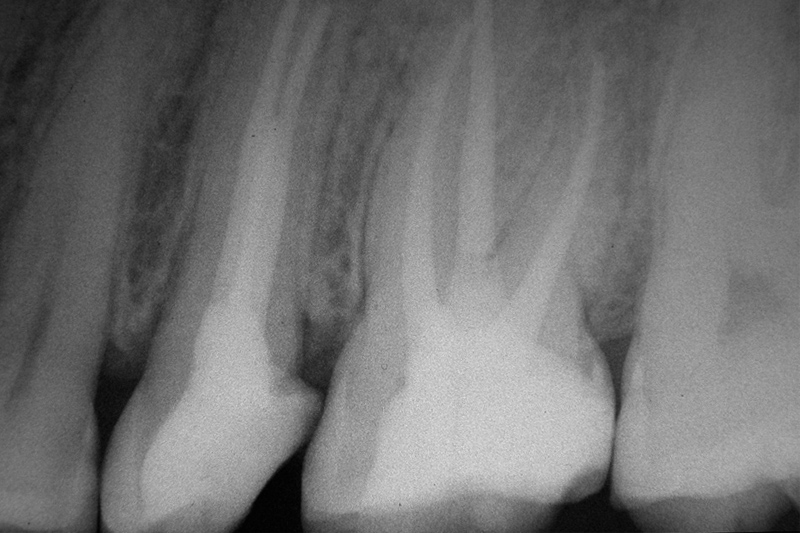

Wurzelkanalbehandlung

Die Endodontie befasst sich mit dem Inneren der Zähne, den Wurzelkanälen und der sogenannten Pulpa, den Nervenbahnen und Blutgefäßen. Der infizierte Zahn wird während der Therapie von innen gereinigt und desinfiziert. Viele Patienten haben Angst vor dieser Behandlung, doch die bei uns verfügbare moderne Technik ermöglicht eine präzise und schmerzfreie Therapie.